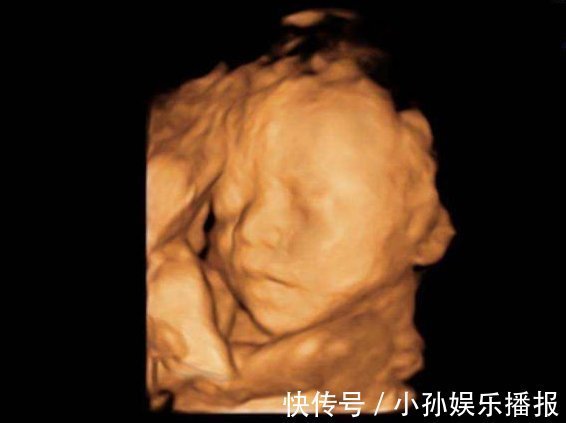

2、四维彩超的本质是什么

四维彩超和其他彩超有什么不同之处呢?四维彩超其实是让三维彩超“动起来”,让孕妈和医生能看到宝宝动起来的样子。不管是二维彩超还是三维彩超,医生用的检查机器都是一样的,只是后期用了特殊的软件。所以了解完这个本质后,孕妈们可以基于这个好好考虑一下做这种检查的次数了。